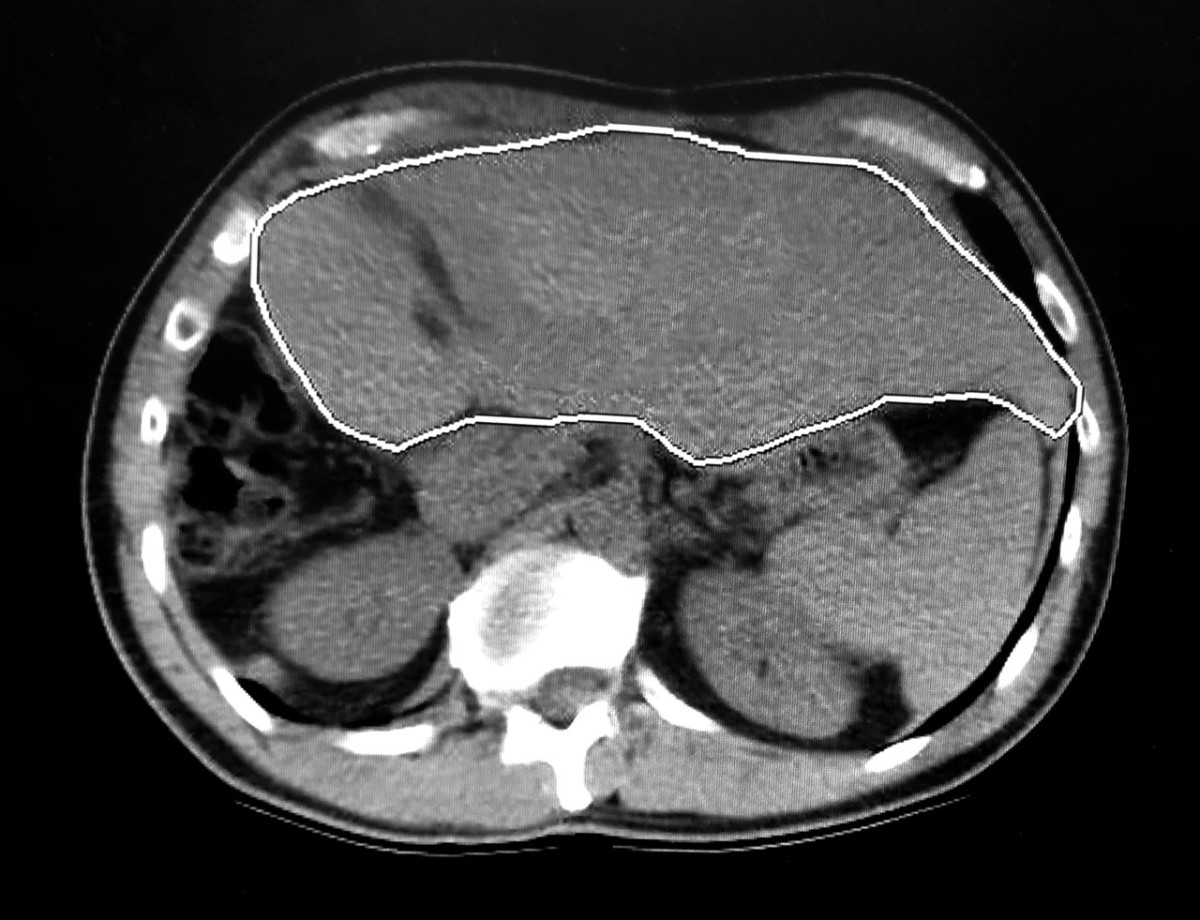

From www.mdpi.com

IJMS Free FullText Effect of Hepatic Pathology on Liver Liver Renewal Time Establishment of foregut liver progenitor cells is essential for liver bud development and occurs through a process called hepatic specification. However, this was probably an oversimplified view, because it has been recently documented that the amount of resected liver really matters and triggers different proliferation stimuli. Depending on the severity of the damage, complete healing can. This review will also. Liver Renewal Time.